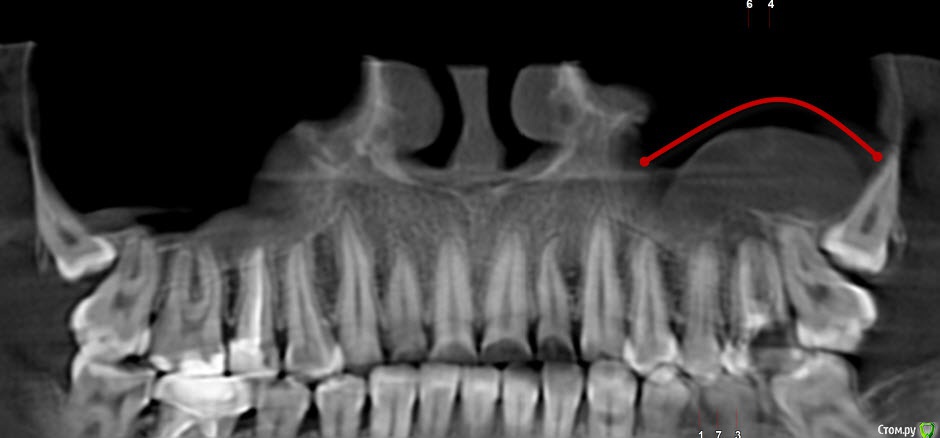

korsa Опубликовано 5 октября, 2016 Поделиться Опубликовано 5 октября, 2016 Всем добрый вечер, прошу помощи. Давным давно, уже и не помню где и кто делал, был удален нерв и запломбирован зуб. 3 недели назад обратилась к врачу с острой болью, не могу наступать, на горячее/холодное реакции нет. Терапевт не смогла вскрыть запломбированный канал и отправила в другую клинику. В другой, мне не стали вскрывать канал(почему не могу сказать, пазухи близко, наговорила мне что-то, для меня не ясное), выписала антибиотики и отпустила, сказав явиться через день. На следующий день зубная боль прошла, но случился сильный отек. На повторном приеме отправила меня к хирургу, та удивилась что канал не вскрыли при первом обращении. В общем, хирург поставила дренаж и отпустила. На 3 день, дренаж сняли, отправили на КТ. После КТ хирург сказала искать врача и попробовать лечить. Но т.к. я простыла, лечение отложилось на 10 дней. После выздоровления, я записалась на консультацию к другому хирургу... Проснувшись в день записи обнаружила снова отек щеки, не такой сильный как в первый раз, но отек(Помогите определить, пожалуйста, действительно он под удаление или все же можно спасти, зуб жевательный, да и вообще, со своим не хотелось бы расставаться(((Первый снимок от 20.09.16И еще, что за потемнение над зубом, такое обширное(под красной линией)Зуб - 26.Второй 14.02.15 - на нем то вообще ни чего нет. Ссылка на комментарий

St. Опубликовано 5 октября, 2016 Поделиться Опубликовано 5 октября, 2016 И еще, что за потемнение над зубом, такое обширное(под красной линией) Реакция слизистой оболочки гайморовой пазухи на хроническое воспаление от 26 зуба Ссылка на комментарий